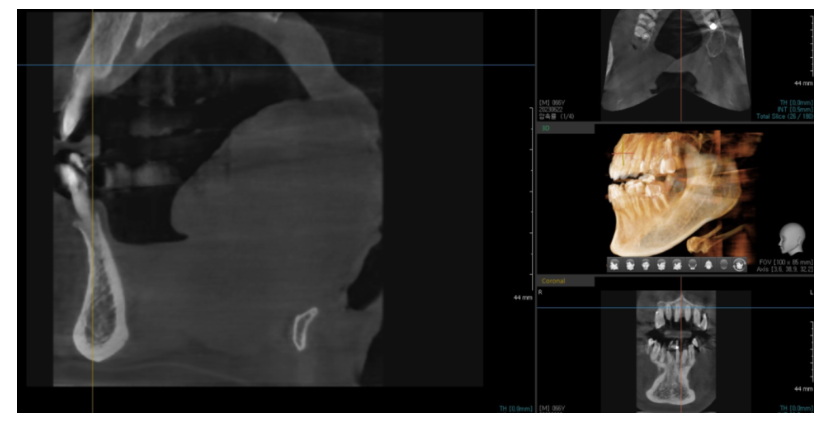

3D CT 촬영 (뼈 두께·높이 확인)

잇몸뼈가 부족하면 뼈이식이 필요하다 설명 드리죠.